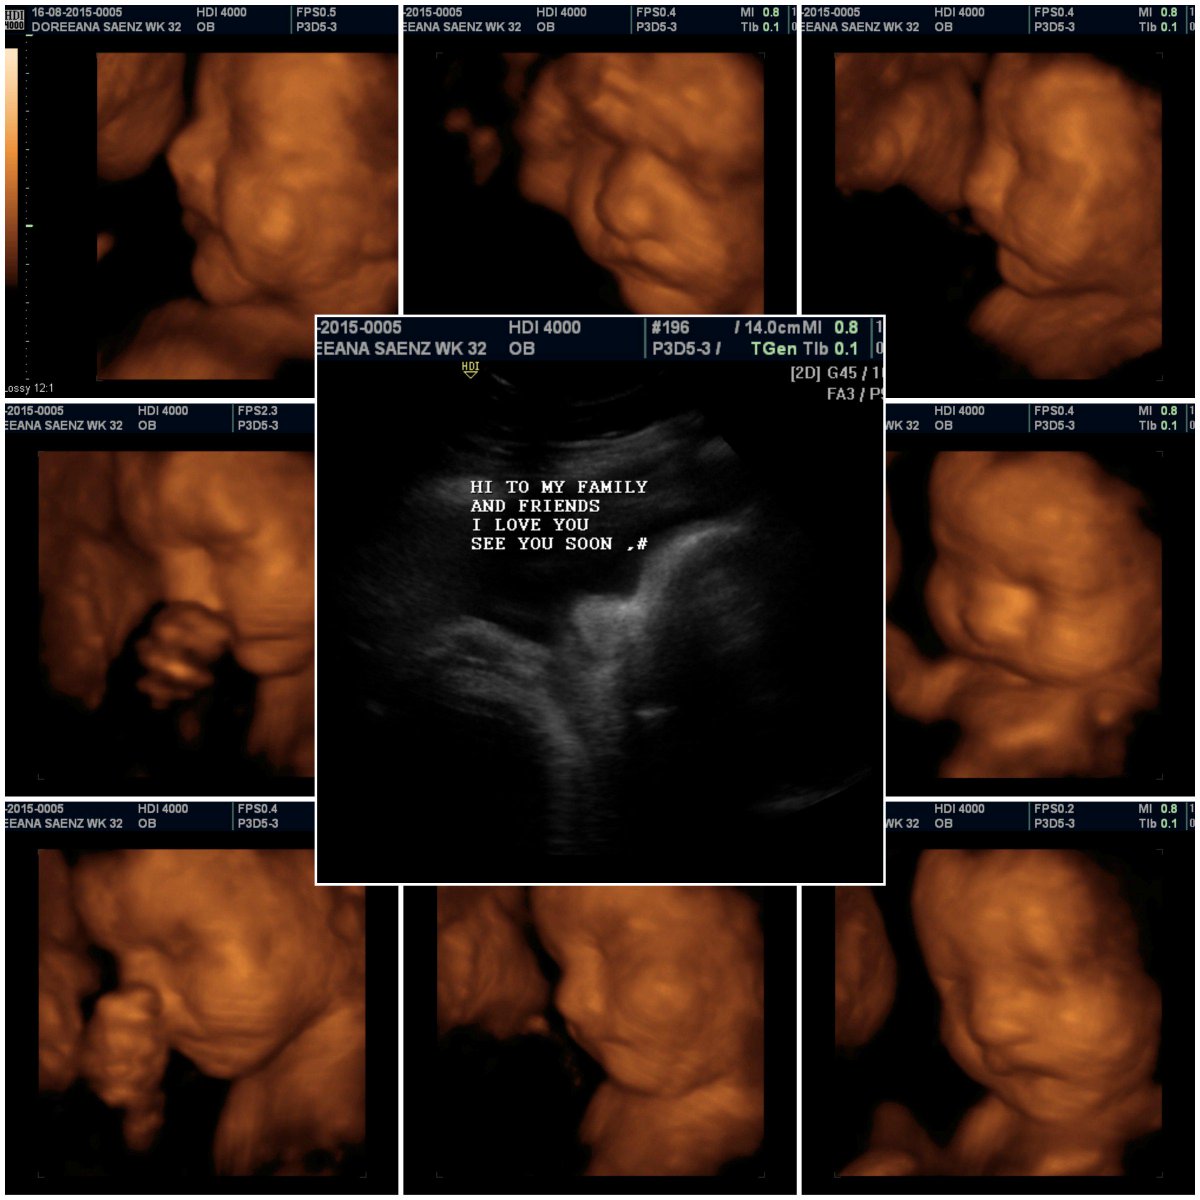

3D Baby Ultrasound on Twitter: “Thank you Doreena and Family http://t …